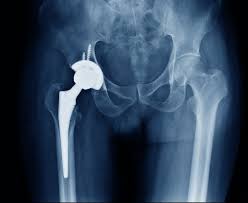

Hip disorders, including arthritis, avascular necrosis, fractures, and joint degeneration, can severely limit mobility and daily function. Therefore, residents of Bhopal experiencing hip pain, stiffness, or difficulty walking often need surgical intervention. Moreover, untreated hip conditions can worsen over time, causing chronic pain and reduced independence. As a result, timely hip replacement surgery becomes necessary to restore quality of life and improve mobility.

Hip replacement surgery replaces a damaged hip joint with an artificial implant, relieving pain and restoring function. Therefore, patients with severe arthritis, joint degeneration, or fractures benefit most from surgery. Moreover, modern techniques reduce surgical risks and accelerate recovery. As a result, residents in Bhopal can regain independence and return to daily activities sooner. In addition, hip replacement prevents further complications, ensuring long-term joint stability.

The hip replacement procedure begins with consultation, imaging, and surgical planning. Therefore, orthopedic specialists assess the patient’s hip condition, overall health, and recovery potential. Moreover, hospital coordinators handle documentation, insurance approvals, and scheduling. As a result, surgery proceeds efficiently and safely. In addition, patients receive personalized care plans, early mobilization guidance, and post-operative monitoring to support quick recovery. Consequently, residents in Bhopal experience structured and patient-friendly treatment.